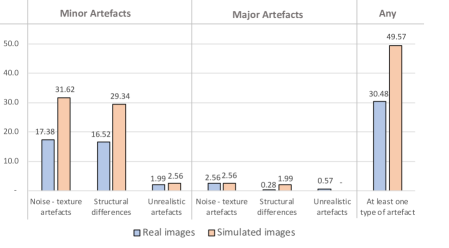

In Fig. 9 we report visual perception results from the survey of experts. These results show that the majority of the artefacts on the simulated images are minor noise/texture artefacts (31.6%) and minor morphological structural differences (29.3%). Only 2.6% were minor unrealistic artefacts, 2.6% major texture artefacts, 1.9% major structural differences, and 0% major unrealistic artefacts. From the results in this figure, we can also see that the simulated images have a slightly higher occurrence of artefacts with respect to the real images. In particular, in the last column, we can see that 30.5% of real images have at least one artefact against 49.6% for the synthetic images.